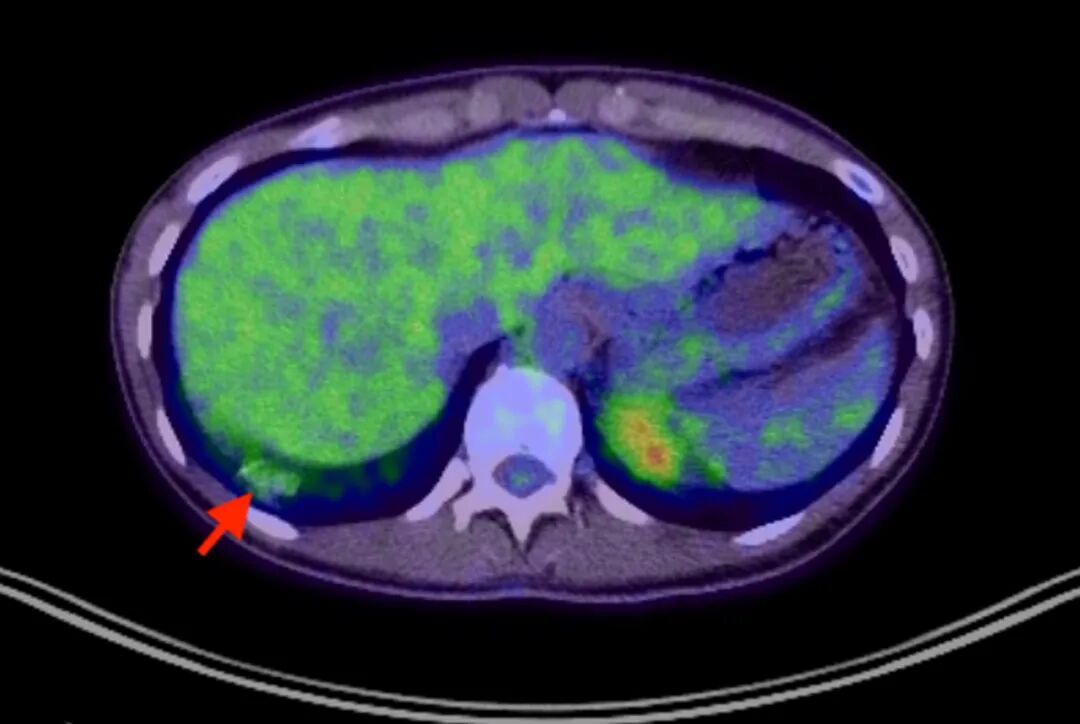

电子计算机断层扫描(CT)/正电子发射计算机断层显像

(PET)扫描显示右下叶部分实性肺结节大小无变化,氟代脱氧葡萄糖

摄取程度较低,最大标准化摄取值(SUVmax)为2.2(图3)。CT/PET扫描未发现异常淋巴结,也未发现肝脏或肾上腺病变。鉴于实性成分≥8毫米的亚实性结节往往具有更具侵袭性的特征,认为有必要进行进一步检查。与患者讨论了经胸壁穿刺活检、导航支气管镜以及电视辅助胸腔镜手术(VATS)活检等方案,患者最终选择了外科手术。

图3. CT/PET融合图像显示,右下叶部分实性结节存在轻度氟代脱氧葡萄糖摄取增高(红色箭头标示)。

CT/PET扫描在诊断弥漫性PAP中通常无明确作用。但有文献报道,在已经进行CT/PET检查的PAP病例中可观察到轻度氟代脱氧葡萄糖摄取。推测其机制可能与PAP发病过程中涉及的炎性细胞对葡萄糖的利用有关。